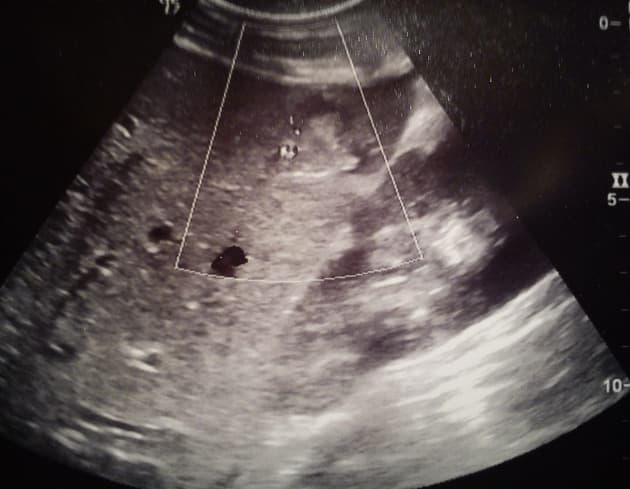

- Dấu hình cành cây giảm tỷ trọng trong gan, lan từ hõm túi mật đến phân đoạn V, đại diện cho tổn thương rách nhu mô gan/huyết khối nhu mô gan (laceration/parenchymal hematoma).

- Vùng tổn thương tương tự nhưng nhỏ hơn nằm liền kề dây chằng liềm.

Tổn thương gan được phân loại là độ II theo thang điểm đánh giá tổn thương gan của Hiệp hội Phẫu thuật Chấn thương Hoa Kỳ (American Association for the Surgery of Trauma - AAST) (tổn thương rách <10cm về chiều dài). Có sự liên quan giữa tổn thương gan và các phát hiện chấn thương bên phải khác như gãy xương sườn, tổn thương phổi, tràn khí màng phổi, tổn thương thận và thượng thận.

- "Dấu hình cành cây giảm tỷ trọng ở gan trên CT sau chấn thương đại diện cho rách nhu mô hoặc huyết khối, thường gặp trong tổn thương độ II theo thang AAST."

- "Gãy các xương sườn dưới bên phải (số 10–12) có liên quan mạnh đến tổn thương gan ẩn, cần đánh giá kỹ gan khi gặp các tổn thương này."

Traumatic Liver Laceration (Gross Pathology) (Vết rách gan do chấn thương (giải phẫu bệnh đại thể))

Liver Trauma Grading According to the 2018 AAST Classification (Phân độ chấn thương gan (sơ đồ))

Hepatic Laceration Due to Penetrating Abdominal Trauma (Vết rách gan do chấn thương xuyên thủng)

Liver Laceration - AAST Grade IV (Vết rách gan - độ IV theo phân loại AAST)

Liver Trauma - AAST Grade IV (Chấn thương gan - độ IV theo phân loại AAST)